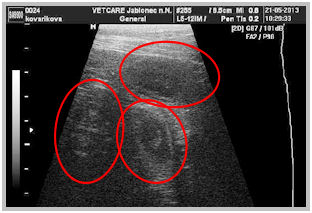

21.5.13 Dnes jsem byla s Atynkou na ultrazvuku. Na fotkách jsem viděla 5 nádherných kuliček, 3 vlevo a 2 vpravo. Paní doktorka Aty vyholila jen malý kousek chlupů na bříšku a tak jsme možná všechna štěnda neviděly a nějaké bude ještě někde schované. Výsledný počet bude překvapení a uvidíme co nám Atynka nadělí.

Na fotkách níže vidíte naše miminka a na spodních fotkách, jak asi nyní vypadají.

border collie speedy dream border collie speedy dream

border collie speedy dreamborder collie speedy dream